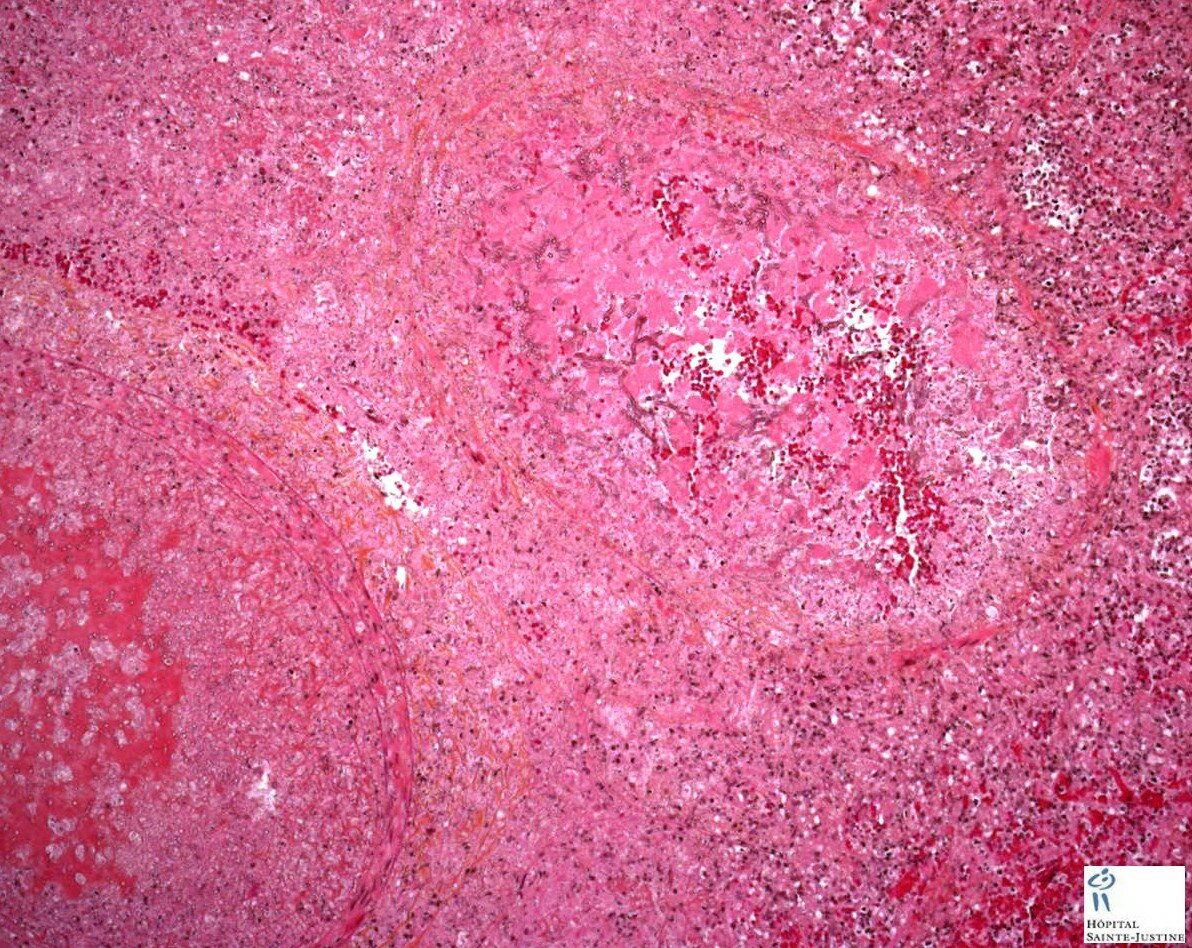

invasive pulmonary aspergillosis

Invasive pulmonary aspergillosis Invasive pulmonary aspergillosis Invasive pulmonary aspergillosis invasive pulmonary aspergillosis invasive pulmonary aspergillosis invasive pulmonary aspergillosis invasive pulmonary aspergillosis invasive pulmonary aspergillosis invasive pulmonary aspergillosis invasive pulmonary aspergillosis invasive pulmonary aspergillosis invasive pulmonary aspergillosis invasive pulmonary aspergillosis invasive pulmonary aspergillosis Invasive pulmonary aspergillosis